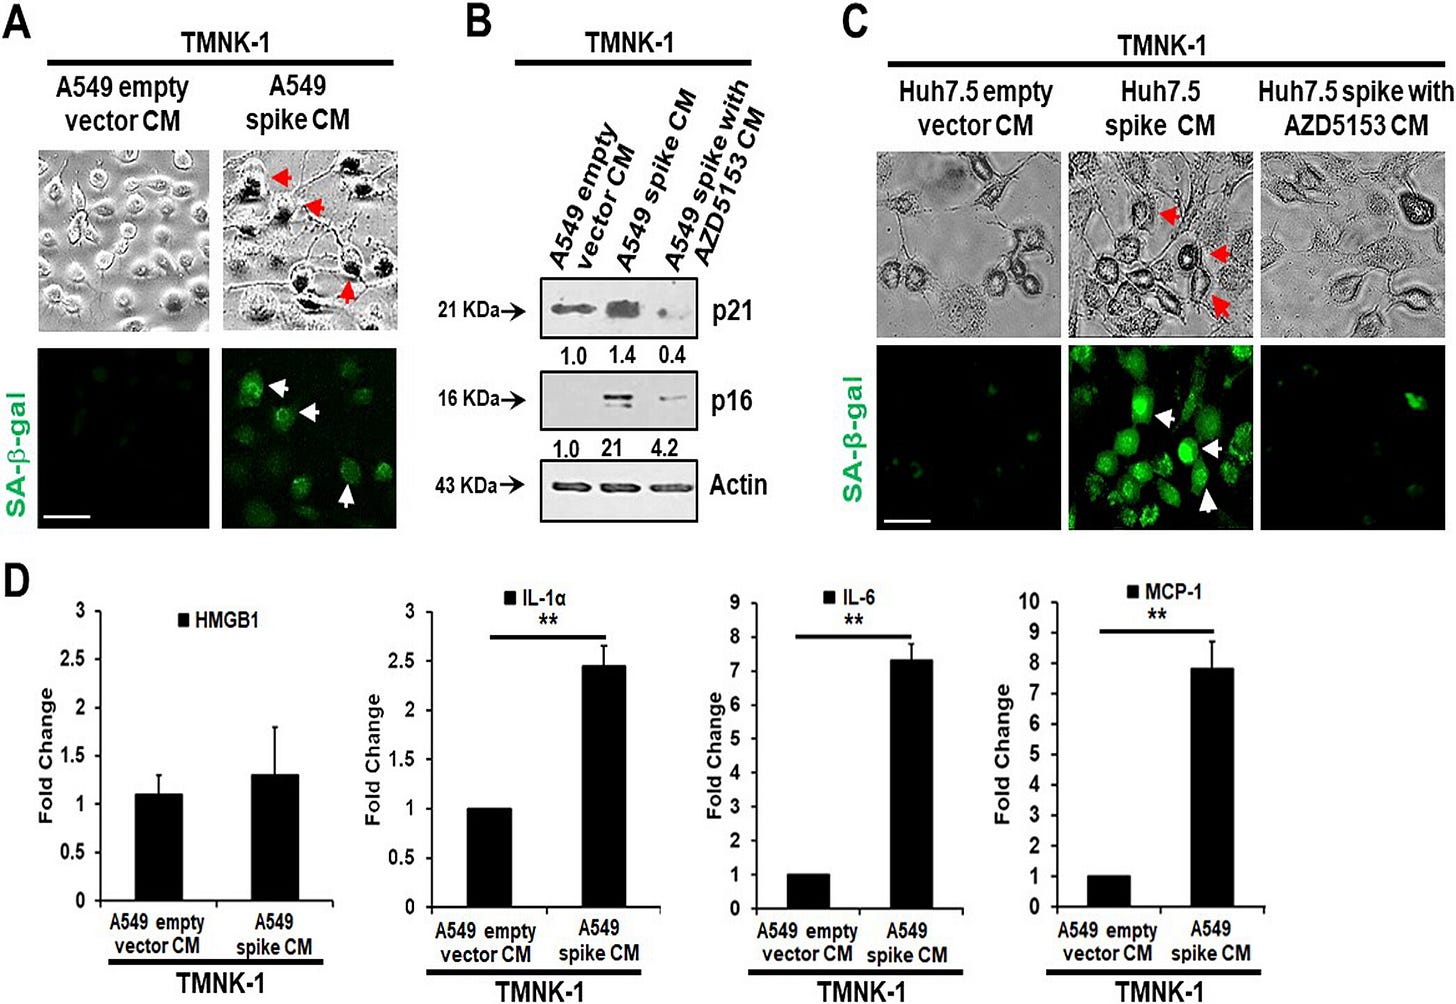

Paracrine effects mean you don’t need spike protein in the cell to induce the senescence-associated secretory phenotype. This should send shivers down your spine, just like any good horror movie.

Senescent cells secrete inflammatory molecules that may induce paracrine senescence in their surrounding cells. We examined whether senescent epithelial cells generated by spike transfection stimulate paracrine senescence in nearby endothelial cells where SARS-CoV-2 spike protein expression is absent. For this, we incubated endothelial TMNK-1 cells with conditioned culture medium (CM) collected from SARS-CoV-2 spike-expressing A549 cells. We observed green fluorescence associated with SA-β-Gal expression in spike CM-treated cells (Fig. 4A). We also observed a strong expression of the senescence markers p21 and p16 from spike CM-treated TMNK-1 cells.

Release of SASP molecules is a signature of the senescence mechanism. An increase in the levels of SASP release-related inflammatory molecules HMGB1, IL-1α, IL-6, and monocyte chemoattractant protein 1 (MCP-1) was also observed in spike CM-treated TMNK-1 cells (Fig. 4D). Thus, our results indicated an induction of paracrine endothelial cell senescence as a bystander effect from SARS-CoV-2 spike-expressing epithelial cells.

Note that the culture medium prepared with BRD4 inhibitor AZD5153 (no spike) doesn’t express the senescence markers p21 & p16. And look closely and you see an 8 fold increase in IL-6 vs the empty vector control: